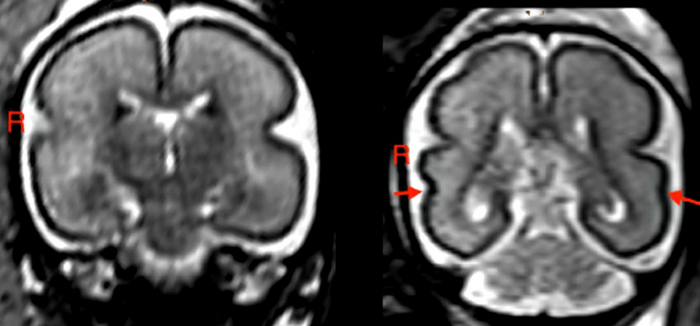

Brain development, known as the fetal total maturation score (fTMS), was significantly reduced compared to healthy, age-matched controls. In particular, the right superior temporal sulcus (STS) was shallower, according to the Austrian team. The STS is involved in social cognition, audiovisual integration, and language perception.

“We found the greatest changes in the temporal brain region and STS,” Dr. Kasprian says. “We know that this region, and specifically the formation of the STS, has a great influence on language development during childhood.”

Delayed fetal brain development could be specifically related to phenomena known as myelination and gyrification. The former is critical to brain and nervous system function in the frontal and occipital lobes.

Gyrification refers to folding of the cerebral cortex which enlarges the surface area with limited space in the skull, enabling an increase in cognitive performance. When gyrification is diminished, functionality is reduced.